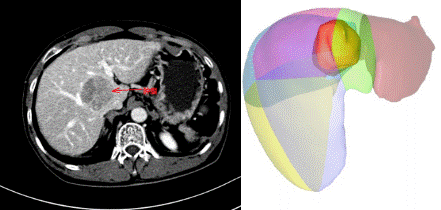

勇闖“禁區(qū)”!——瀘州市中醫(yī)院再攀技術高峰,成功開展“剝蛋黃”手術經(jīng)肝臟正中裂將肝臟劈開,在布滿粗大血管的肝臟背側,將腫瘤從被血管包繞的肝臟尾狀葉切除,并最大限度保留正常肝組織。該手術猶如“火中取栗”,要求手術醫(yī)生必須有“庖丁解?!卑愕木珳剩虼?,該手術方式被東方肝膽醫(yī)院的周偉平...